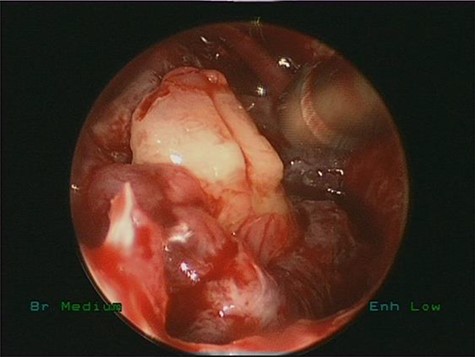

Intraoperative endoscopic view of frank pus draining the right maxillary sinus

Endoscopic removal of the ectopic molar tooth (Fig. 3) along with dissection and removal of both cysts. With the help of different angled endoscopes and forceps.

Intraoperative endoscopic view of ectopic tooth and the cyst, the patient’s symptoms were resolved completely postoperatively and remained symptoms free for 4 years follow-up